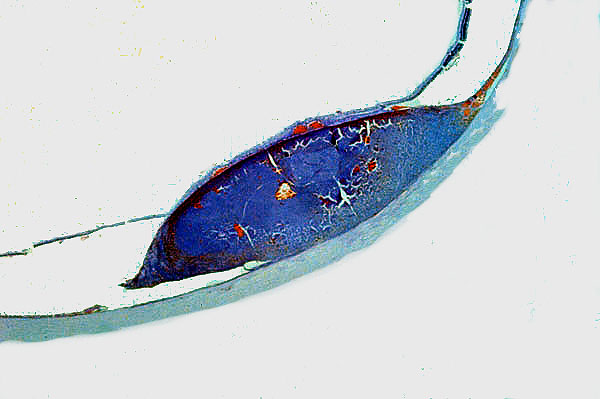

Uveal melanoma, scanning power, posterior segment

Scanning power, posterior segment uveal melanoma

Where does the uveal melanoma arise relative to the retina? The retinal pigmented epithelium?